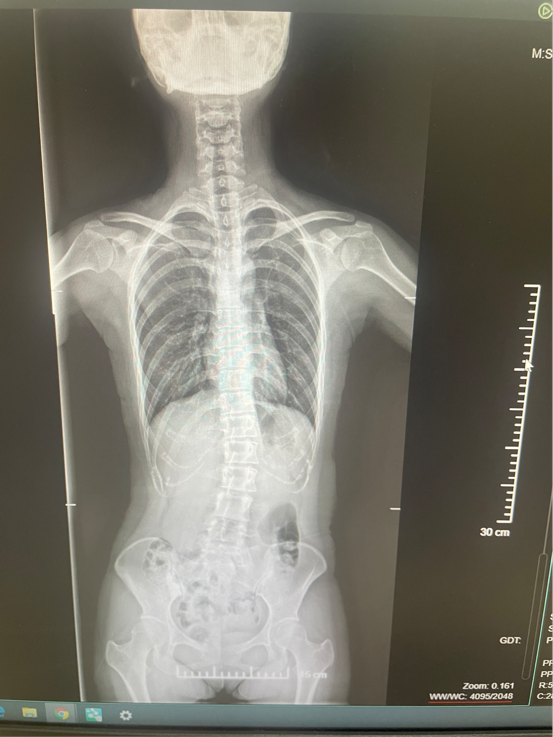

我心里太清楚这意味着什么。脊柱侧弯患者打无痛,穿刺难度大、失败率高,很多麻醉医生都会望而却步。我一直以为自己注定要“裸奔”上产床,没有无痛、没有退路。那些年我听说过太多产妇在剧痛中挣扎,我害怕自己也会成为其中之一。

就在我几乎放弃顺产念头的时候,徐矿总医院的麻醉师薛刚主任给了我意想不到的转机。他得知我的情况后,认认真真地帮我反复阅片。一次、两次、三次……他不厌其烦地研究我的脊柱影像,寻找最佳的穿刺路径。每一次看完片子,他都会给我打电话,耐心解释、真诚鼓励。